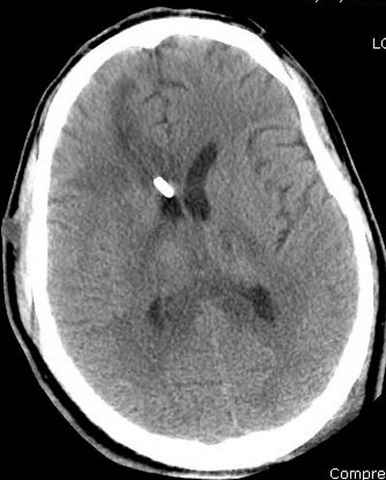

больному 42, автоавария, политравма, открытая черепномозговая травма, безсознании, открытый перелом бедра, размозжение мягких тканей, дефект кожи на передней поверхности бедра около 13 см2 от ожога, компартмент синдром.

Наблюдается службой травмы и нейрохирургии (ICP) Increased Intracranial Pressure by ventricular cateter

больной без сознания, со слов нейрохирурга, наблюдается положительная динамика в нейрохирургическом статусе.

монииторинг